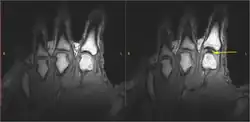

Havia várias hipóteses para explicar a crepitação das articulações. A cavitação do líquido sinovial tem algumas evidências que a apoiam.[10] Quando uma manipulação da coluna vertebral é realizada, a força aplicada separa as superfícies articulares de uma articulação sinovial totalmente encapsulada, o que, por sua vez, cria uma redução na pressão dentro da cavidade da articulação. Nesse ambiente de baixa pressão, alguns dos gases dissolvidos no fluido sinovial (que são encontrados naturalmente em todos os fluidos corporais) saem da solução, formando uma bolha ou cavidade (tribonucleação), que rapidamente se colapsa sobre si mesma, resultando em um som de "clique".[11] Acredita-se que o conteúdo da bolha de gás resultante seja principalmente dióxido de carbono, oxigênio e nitrogênio.[12] Os efeitos desse processo permanecerão por um período conhecido como "período refratário", durante o qual a articulação não pode ser "estalada novamente", que dura cerca de 20 minutos, enquanto os gases são lentamente reabsorvidos pelo fluido sinovial. Há algumas evidências de que a hipermobilidade dos ligamentos pode estar associado a uma maior tendência à cavitação.[13]

Em 2015, uma pesquisa mostrou que as bolhas permaneceram no fluido após a crepitação, sugerindo que o som da crepitação foi produzido quando a bolha dentro da junta foi formada, e não quando ela entrou em colapso.[9] Em 2018, uma equipe na França criou uma simulação matemática do que acontece em uma junta logo antes de ela estalar. A equipe concluiu que o som é causado pelo colapso das bolhas, e as bolhas observadas no fluido são o resultado de um colapso parcial. Devido à base teórica e à falta de experimentos físicos, a comunidade científica ainda não está totalmente convencida dessa conclusão.[3][14][15]